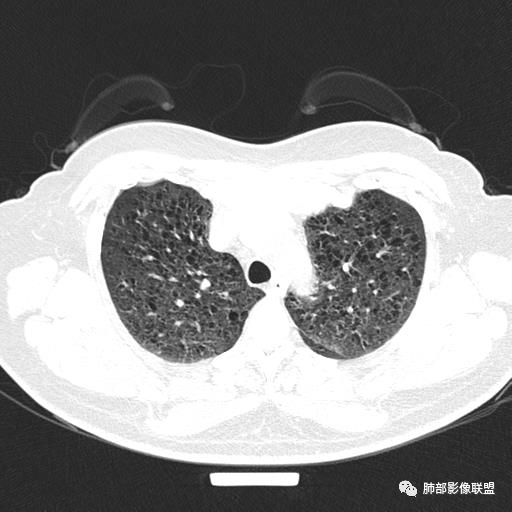

双肺弥漫囊腔,累及肋膈角,囊腔形态相对规则单一。

CT平扫示双肺弥漫分布大小不等囊状薄壁透光区,无内、中、外带分布差异,间质稍示增厚。拟LAM

中年女性育龄期妇女,咳嗽气喘,无吸烟史,有苯吸入史。影像:双肺弥漫均匀小囊腔,无明显分布优势,囊腔形态欠规则,壁薄,部分囊腔边缘血管征,伴双肺弥漫磨玻璃影,无结节,考虑lam,鉴别苯中毒肺损伤,囊腔多有分布优势,小叶中心分布为主,形态规整等

CT表现:双肺弥漫大小不等的薄壁囊腔,囊壁<2mm,外形规则,血管影多位于囊腔周围,囊腔之间肺组织正常,随着疾病进展到晚期,囊腔变大、增多,不可胜数,囊腔可融合成较大的囊,与肺气肿相似,形成间质性肺纤维化。部分病例可出现结节影。